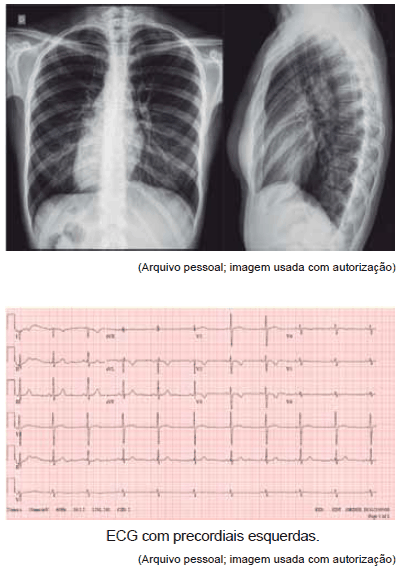

Paciente de 16 anos foi encaminhada ao Pronto-Socorro com quadro de dor torácica, palpitações e palidez cutânea associadas. Ao exame físico, notou-se semiologia cardiovascular normal, porém com ausculta das bulhas em hemitórax direito. Foram solicitados os seguintes exames:

O diagnóstico mais provável é:

Observe as seguintes figuras.

Elas são compatíveis com qual diagnóstico?